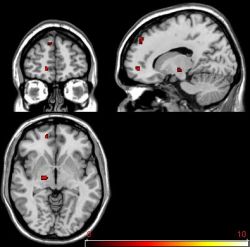

Related parts of the prefrontal cortex are involved in so-called executive functions – planning, and monitoring and vetoing our every-day actions and we have shown that alcoholics with repeated detoxifications are impaired in such functions. In alcoholic patients, ability to monitor ongoing behaviour is particularly important in the conflict between the executive decision to abstain, and the desire to drink. We developed a computer game in which the player could win money if they responded when either of two abstract symbols appeared on the screen; however, when both symbols appeared together, instead of winning twice as much, they lost money. This way, the players had to decide whether to take a reward, or to abstain. Multiply-detoxified alcoholics were just as good as normal subjects in responding to win money, but they were unable to stop responding when they needed to apply the information that the combined symbol meant they would lose money. During this game, healthy individuals showed activation of particular regions of the prefrontal cortex when the mixed information told them button pressing would lose them money (see brain images below), and precisely the same areas were found to be shrunken in the multiply detoxified patients, so they don’t function as well in controlling the urge to press for reward (Duka et al, 2011).

A. fMRI image obtained from healthy volunteers during performance of the incentive conflict computer game showing activation in the ventromedial prefrontal cortex. This area is activated when the volunteer has to decide not to respond when presented with two symbols, which when presented singly inform that money can be won.

B. Exactly the same area (indicated with the number 2) shows shrinkage in alcoholic patients who have undergone several episodes of detoxification